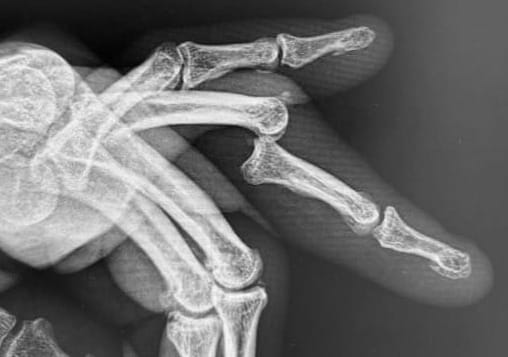

X-rays demonstrated a volar dislocation of the left ring finger PIP joint, with two small osseous fragments visible within the dorsal joint recess. The dislocation was easily reduced under a local anaesthetic ring block.

Post-reduction, the joint was clinically unstable and would re-dislocate with flexion of the PIP joint. The finger was immobilised in extension using a splint, and the patient was referred to hand therapy, with the instability noted in the referral. The report of the post reduction film suggested that there was a minor avulsion from the head of the proximal phalanx.

One week later, the patient re-presented with another volar dislocation of the same PIP joint. The hand therapist had replaced the original Zimmer splint with a thermoplastic splint. The patient reported striking his hand against a wall after waking suddenly. The dislocation was again reduced under ring block. Following this second reduction, the finger demonstrated a mild Boutonnière deformity. This time the radiology report suggested that the avulsion fragment was from the base of the middle phalanx.